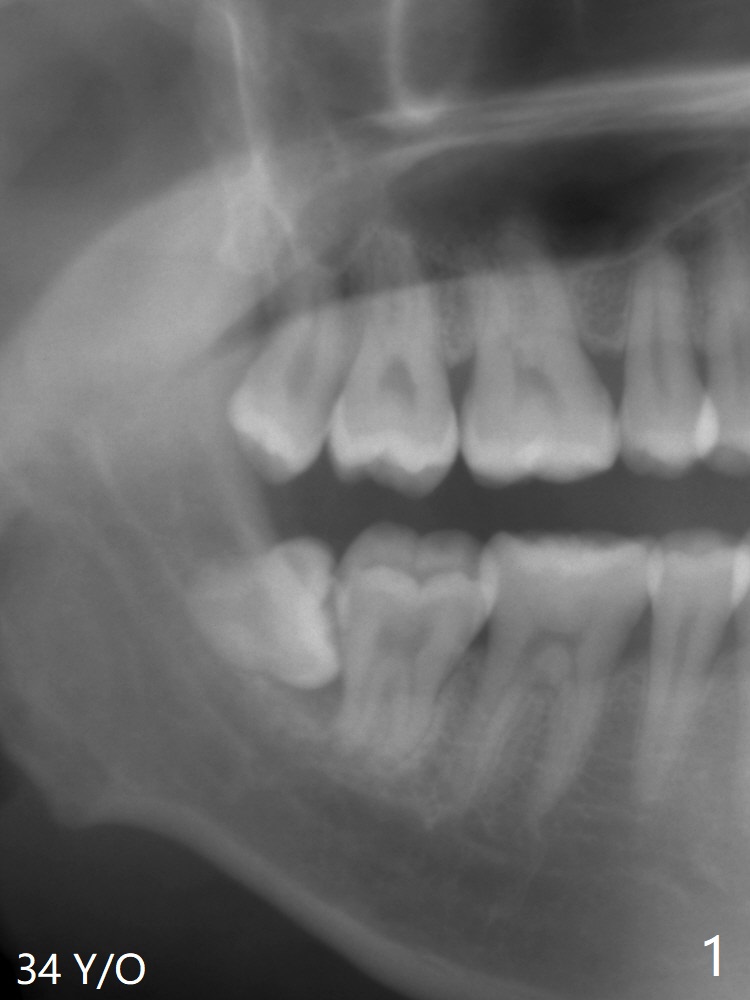

A 34-year-old man requests extraction of #1 and 32 (Fig.1). With placement of Osteogen Plug at #32 after extraction, the socket is filled with bone 4 years postop (Fig.2).